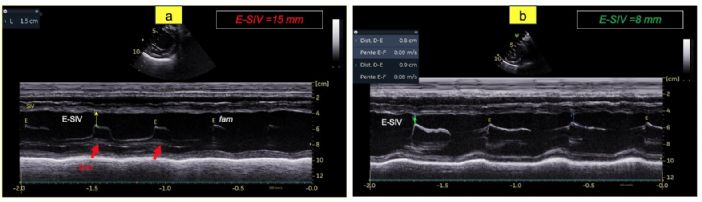

- La nette augmentation de la distance entre l'onde E mitrale et le septum interventriculaire (E-SIV) égale à 15 mm (VU chiens sains 7,7 mm) (Figure 3A) ;

- Une réduction substantielle de la distance E-SIV par comparaison avec J0 (Figure 3B versus 3A) ;